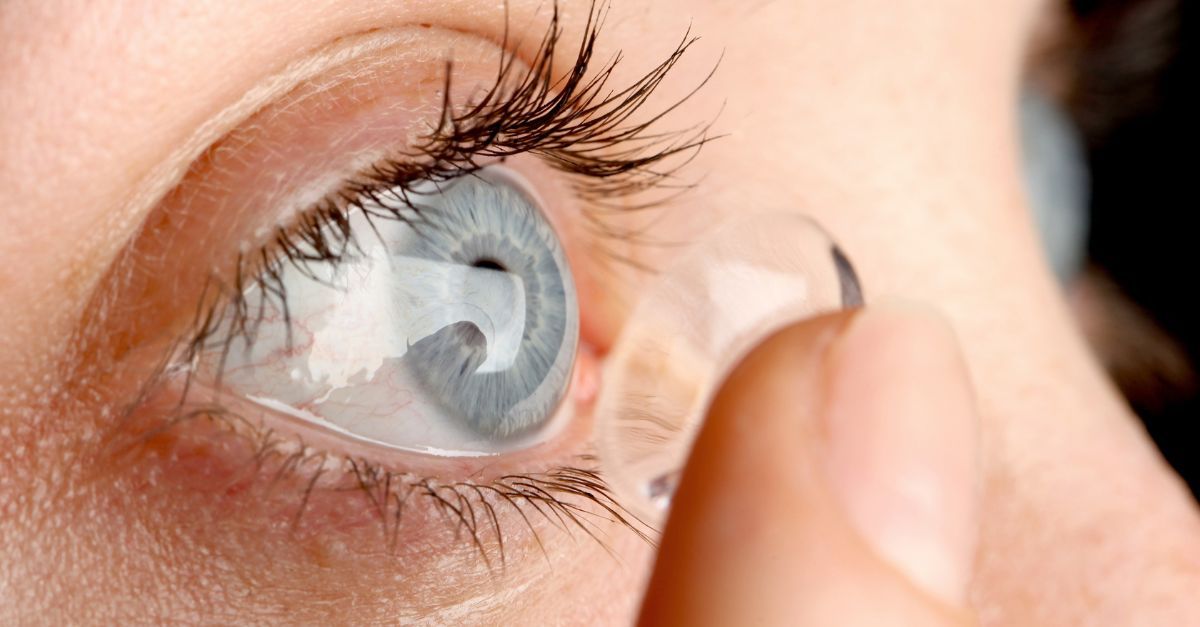

Wearing #ContactLenses whilst in the water can lead to all sort of eye problems, including irritation, infection, and more serious complications like corneal ulcers and acanthamoeba keratitis, which can lead to permanent blindness. Find out more bit.ly/3kI8HxI